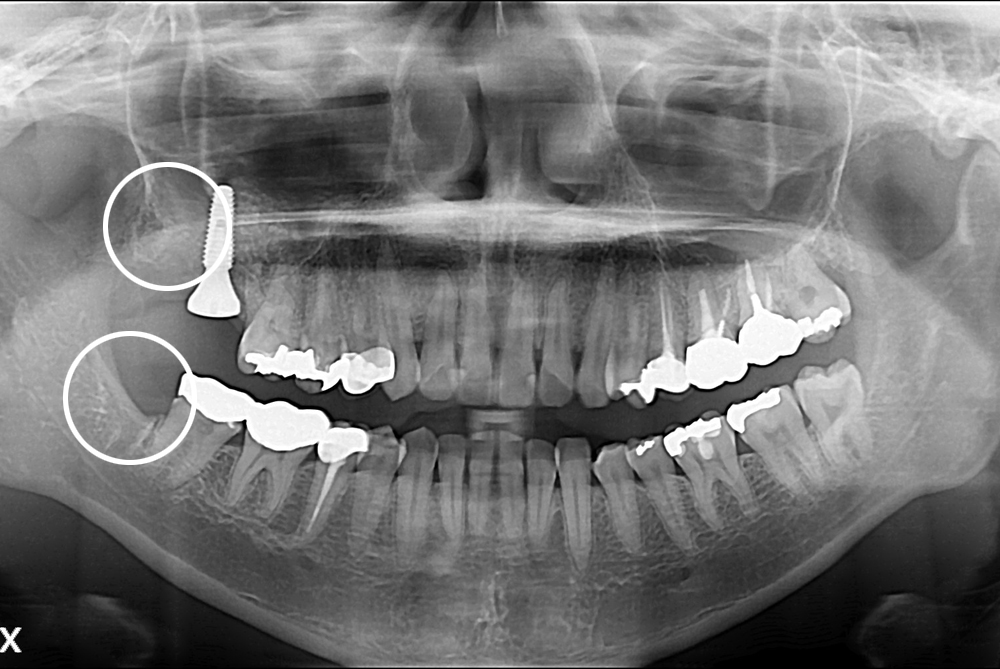

치료사례

세종치과의 진심 어린 치료는 결과로 말합니다.

실제 내원하신 환자분들의 치료 전·후 사례를 확인해보세요.

모든 치료사례 전후사진은 환자분의 동의하에 촬영되었습니다.

모든사진은 동일 환자분의 전후모습을 촬영하였으며, 사진의 밝기조절 외에 임의 수정이 없음을 알려드립니다.